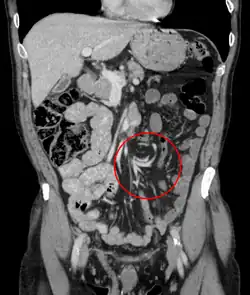

Coronal view of sigmoid volvulus with "whirlpool sign" -

CT scan of a cecal volvulus